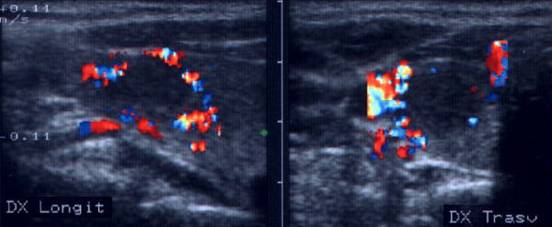

Apexul lobului drept, proiectie longitudinala si trasversala.

Femeie 58 ani. Maladia Graves in tratament cu

metimazol.

Nodul unic in apexul lobului drept, de 11x14x20mm (1,5 cc), hipoecogen, cu

contur difuz

Nu s-a efetuat citoaspiratie.

Aceeasi pacienta. La ecodoppler color - vascularizatie

periferica, avascular intralezional.

Ecopowerdoppler confirma absenta vascularizatiei interne.